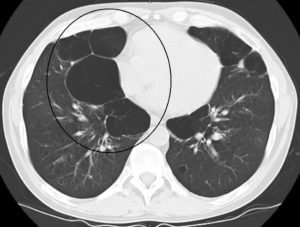

При диагностировании буллезной эмфиземы легких учитываются данные клинических, функциональных и рентгенологических исследований. Рентгенография легких не всегда позволяет выявить буллезную эмфизему легких.

В то же время, возможность лучевой диагностики существенно расширяет применение компьютерной томографии легких. На томограммах буллы определяются как тонкостенные полости с четкими и ровными контурами.

При сомнительном диагнозе достоверную информацию позволяет получить торакоскопия.

- компьютерную томографию;

- Томография и рентгенография.